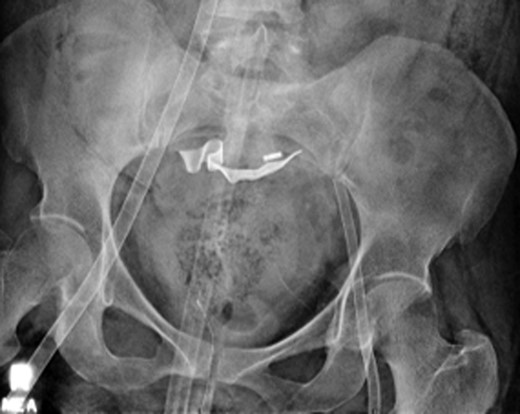

Once stable, imaging confirmed PE (Fig. 2) with a RV to left ventricle (LV) ratio of 2.1 (Fig. 3). The patient was then admitted to the ICU requiring inotropic support. Approximately 4 h later, the patient had concerning features of abdominal compartmental syndrome with increase abdominal distention and bladder pressures >25 mmHg was noted. Repeat imaging showed large volume hemoperitoneum emanating from the left hepatic lobe (Fig. 4). The patient underwent a decompressive laparotomy with a non-anatomic liver resection of segments I and II and temporary abdominal closure. Due to concerns of distal limb ischemia of the arterial cannulation site, an 8-Fr reperfusion cannula was placed in the left superficial femoral artery (SFA).

CTA chest showing significant pulmonary embolic clot burden occluding the right and left upper lung lobes.